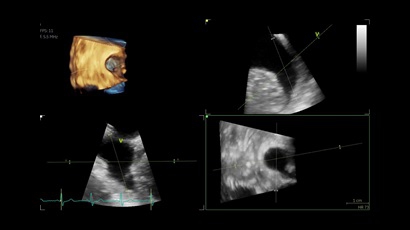

• Vivid IQ 4D с поддержкой технологии объемной реконструкции

• Передовые технологии, такие как 4D чреспищеводная эхокардиография, ЭКГ, стресс-эхо, внутрисердечная ультразвуковая эхокардиография, тканевый доплер и другие.

• 4D AUTO AVQ - модуль автоматического выравнивания, сегментации и обсчета размеров кольца аортального клапана по объемным данным.

• 4D AUTO LVQ - модуль расчета массы миокарда ЛЖ на основе данных 4D-исследования.